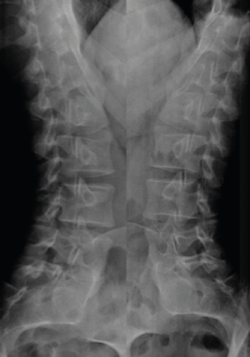

Otros hallazgos radiológicos frecuentes, como las anomalías congénitas de transición lumbosacra, espondilolistesis, secuelas de epifisitis, la espina bífida oculta, las escoliosis leves o moderadas, la hiperlordosis, espondiloartropatía, etc., se encuentran casi por igual en pacientes con y sin dolor lumbar (Figuras 5, 6 y 7)(22,23).

Figura 5. Espondiloartropatía degenerativa.

Por otro lado, alteraciones degenerativas denominadas como “enfermedades” que forman parte de síndromes radiculares asociadas con dolor lumbar se observan con frecuencia en asintomáticos.